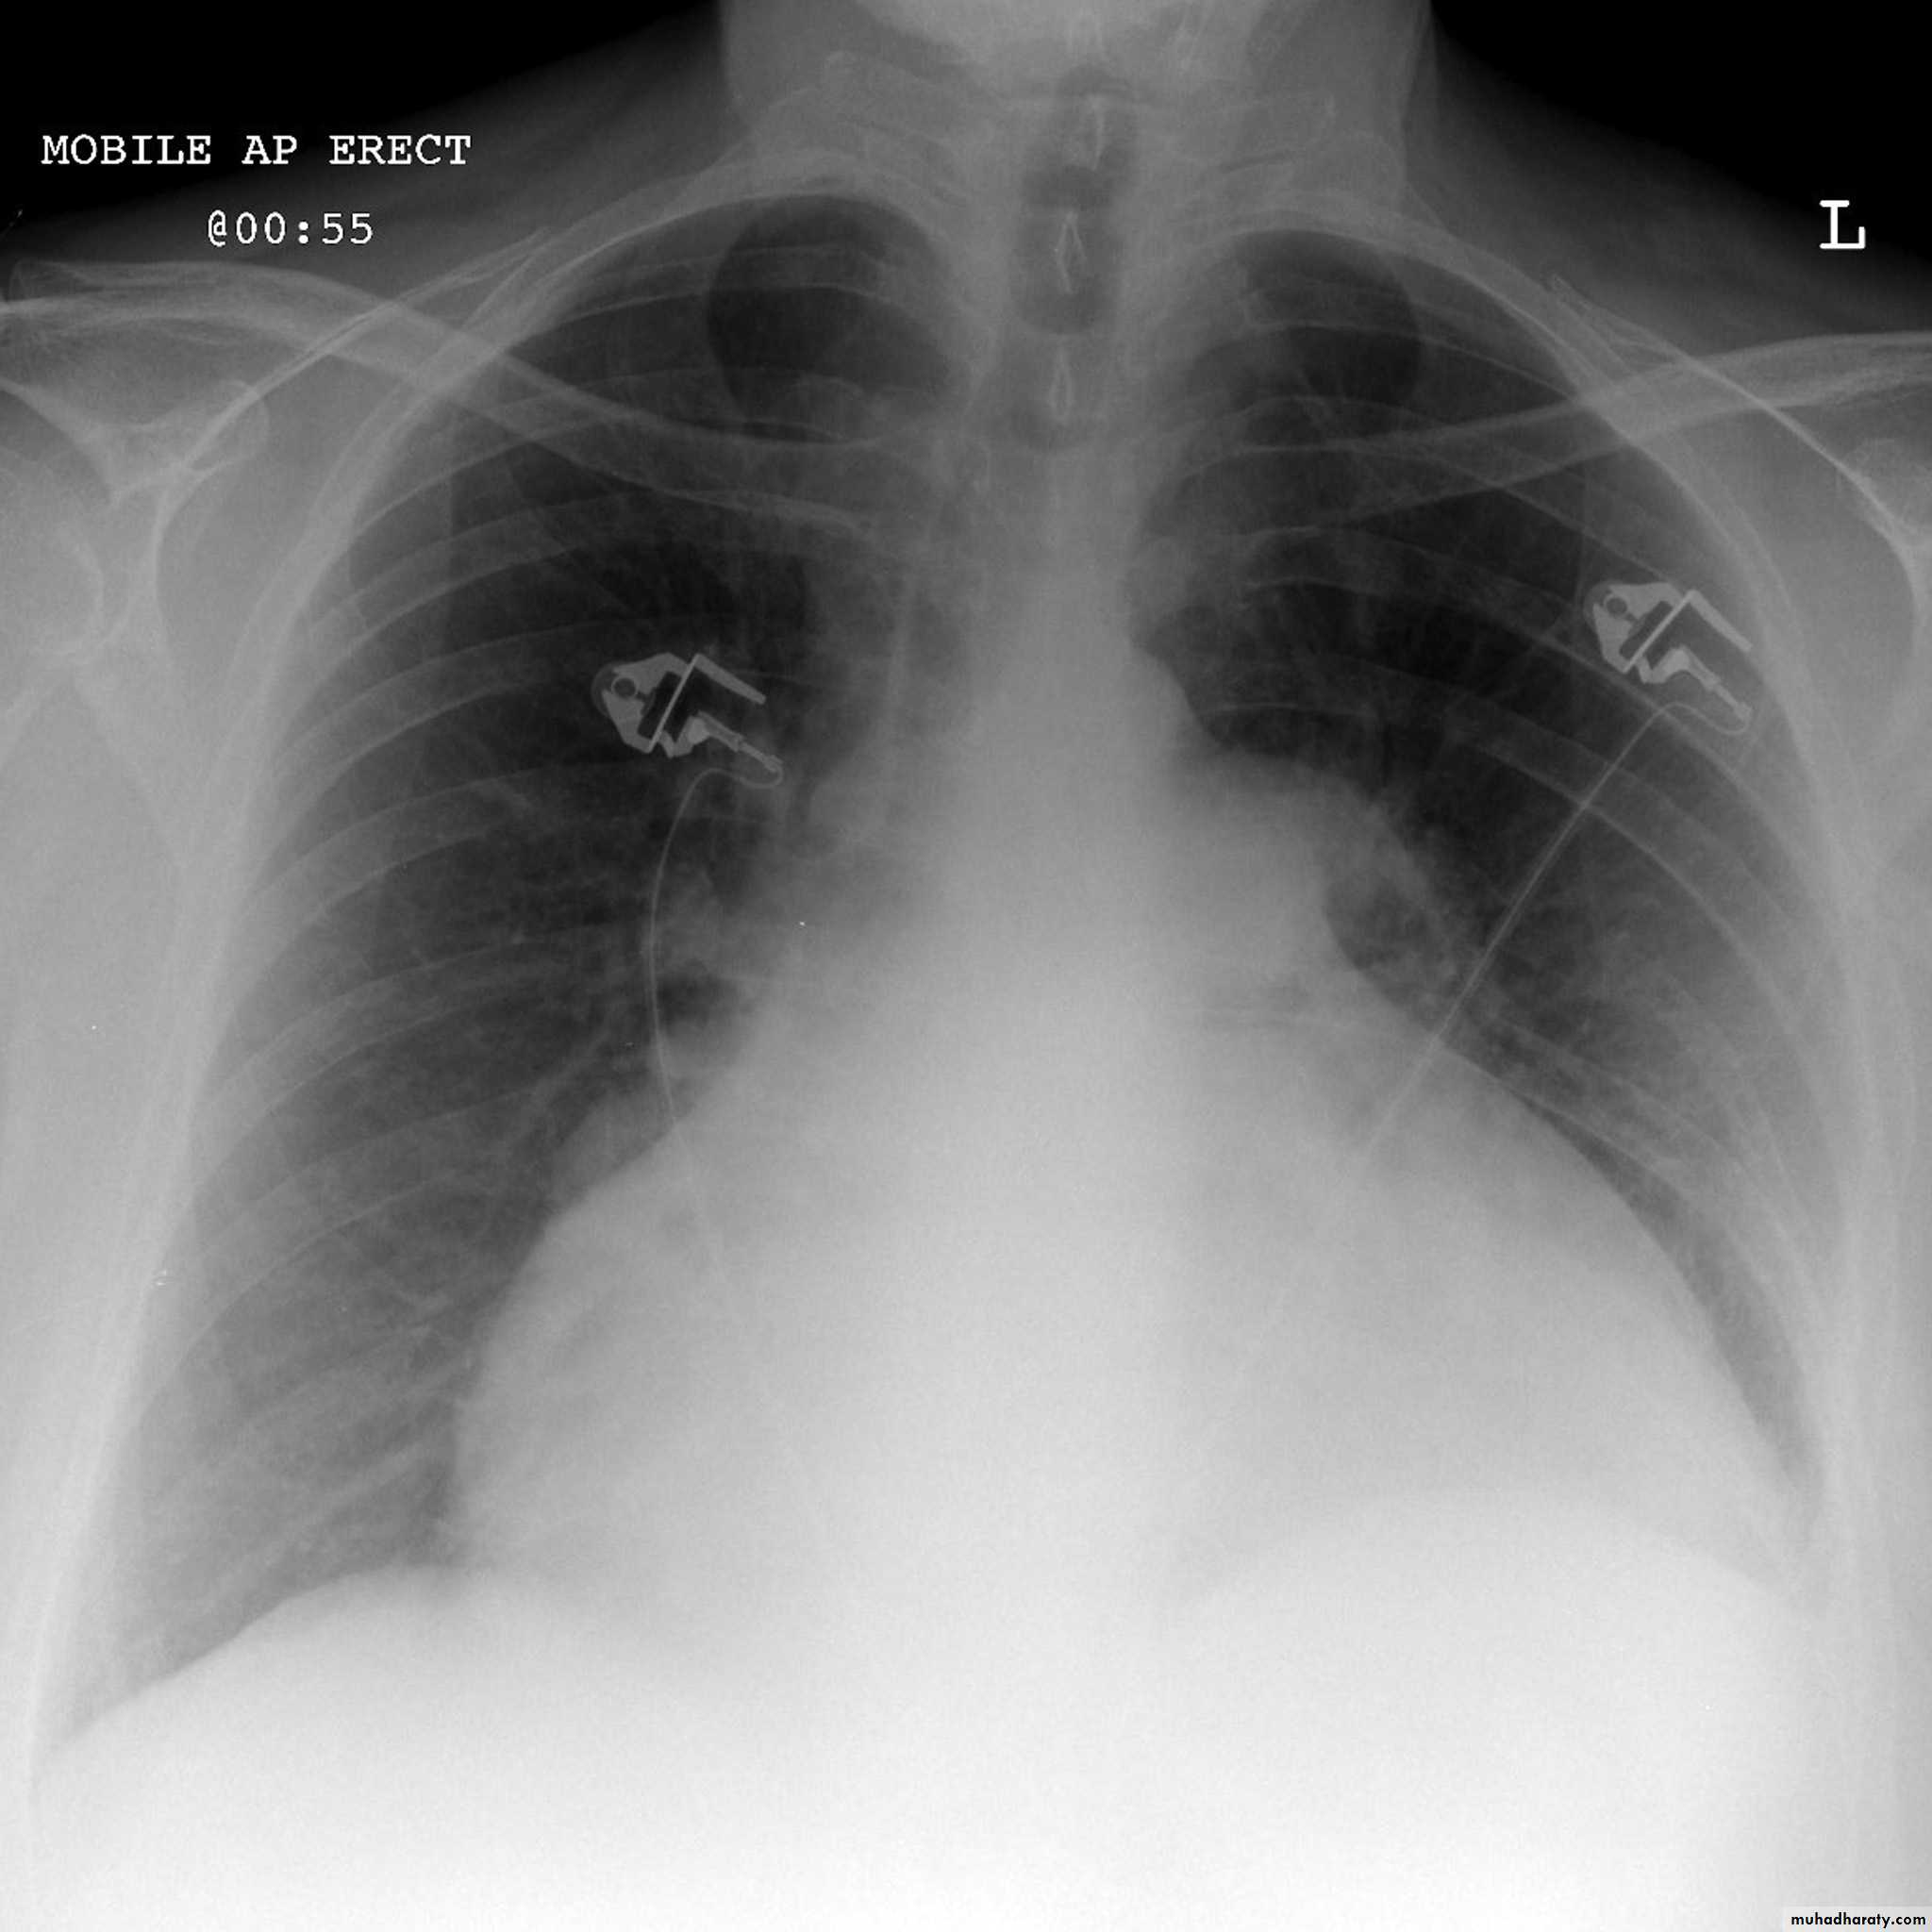

Cardiothoracic ratio (CTR) = Cardiac Width : Thoracic Width

A CTR of greater than 1:2 (50%) is considered abnormal. This however, assumes the projection is Posterior-Anterior (PA), and that cardiac size is not exaggerated by factors such as patient rotation or an incomplete breath in .

The cardiothoracic ratio aids in the detection of cardiomegaly, or more broadly,enlargement of the cardiac silhouette. .

Enlargement of the cardiac silhouette on chest x-ray can be due to a number of causes :

cardiomegaly (most common cause by far)pericardial effusion

anterior mediastinal mass

prominent epicardial fat pad